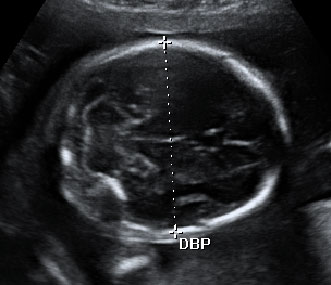

La medición del diámetro biparietal es muy importante en la semana 20 de embarazo. Con esta medida de la cabeza del bebé (sección transversal de la cabeza fetal en el plano adecuado) tal y como vemos en la imagen, el ecografista comprueba el correcto desarrollo de la cabeza fetal.

para la medición del diámetro biparietal (DBP)